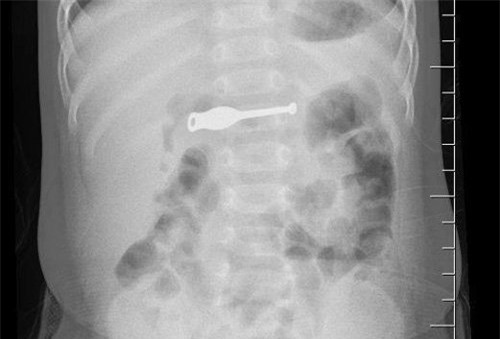

Theo BS Trần Thị Minh Lý, Phó giám đốc bệnh viện, bé Khánh nhập viện trong tình trạng đau bụng, quấy khóc. Khi chụp X-quang, các bác sĩ phát hiện có dị vật kim loại dài khoảng 10cm ở dạ dày.

Chiếc que lấy ráy tai dài 10cm nằm trọn trong bụng bệnh nhi |

Đánh giá sơ bộ dị vật không có cạnh sắc nhọn, các bác sĩ đã chỉ định nội soi kịp thời gắp ra, may mắn không có tổn thương nào. Đây là một trong những bệnh nhi nhỏ tuổi nhất nuốt phải dị vật cứng, nguy hiểm.